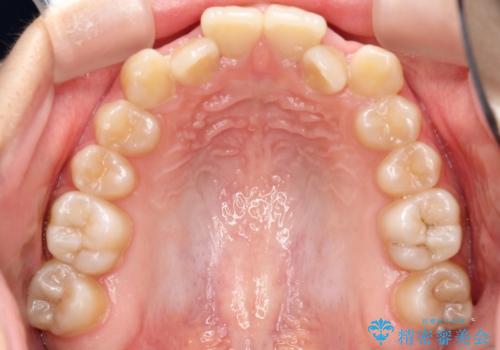

- 前歯のデコボコ(叢生)と、前歯が上下逆の咬み合わせ(反対咬合)を主訴にご来院されました。精密検査の結果、歯列全体のスペースが不足していることが判明。患者様のご希望に合わせ、透明で目立ちにくい**インビザライン(マウスピース矯正)**による治療計画を立案しました。歯を抜かずに、歯列全体を奥(遠心)へ移動させることで、歯が並ぶスペースを確保し、叢生と反対咬合を同時に改善することを目指します。

今回の矯正治療では、透明なマウスピース型の装置インビザラインを使用しました。この装置は目立たず、取り外しが可能なため、食事や歯磨きも普段通り行えます。治療は、緻密な治療計画に基づき、段階的に作製されたマウスピースを交換していくことで、遠心移動という方法で奥歯から徐々に歯列全体を後方へ動かしました。これにより、不足していたスペースを確保し、前歯のデコボコを解消。同時に、上下の歯の前後的な関係を改善することで、反対咬合も正常な咬み合わせへと導きました。見た目も機能も改善し、自然で美しい笑顔を獲得していただけました。